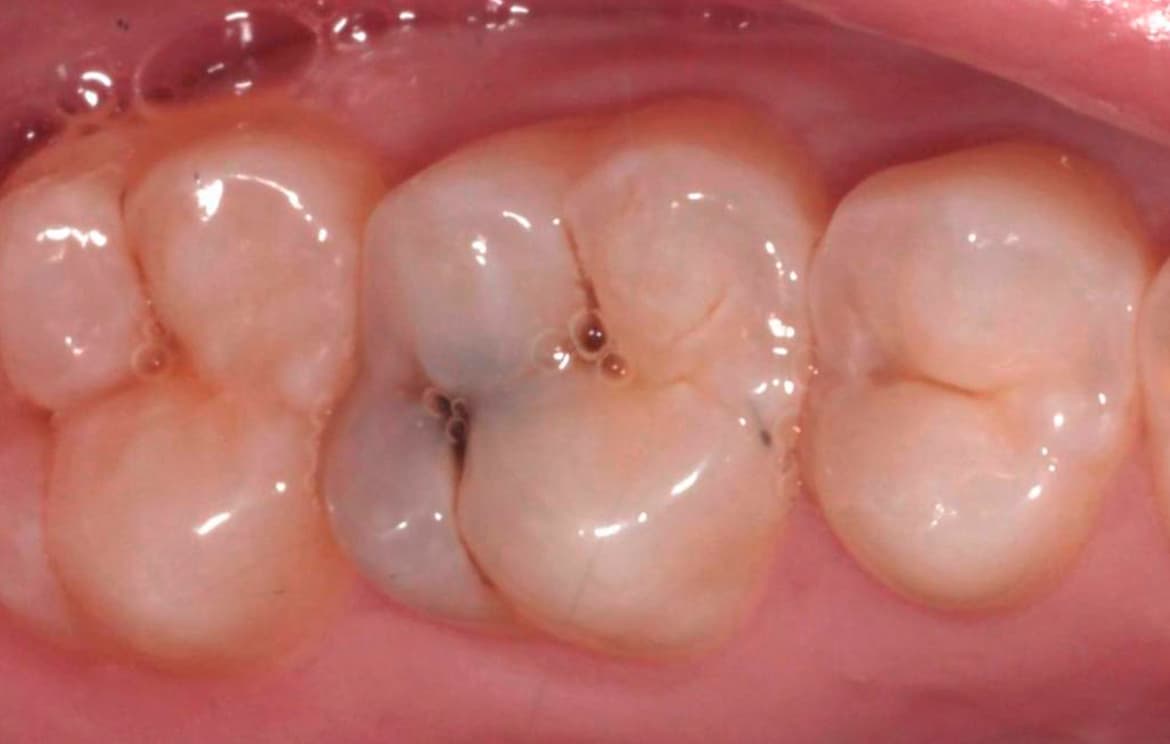

Наши работы